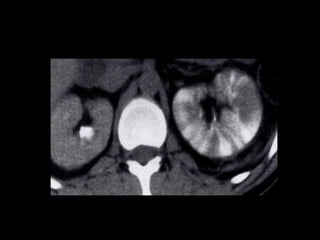

CT:

CT demonstrates a well-defined

heterogeneous mass with areas of

calcification, necrosis and

hemorrhage.